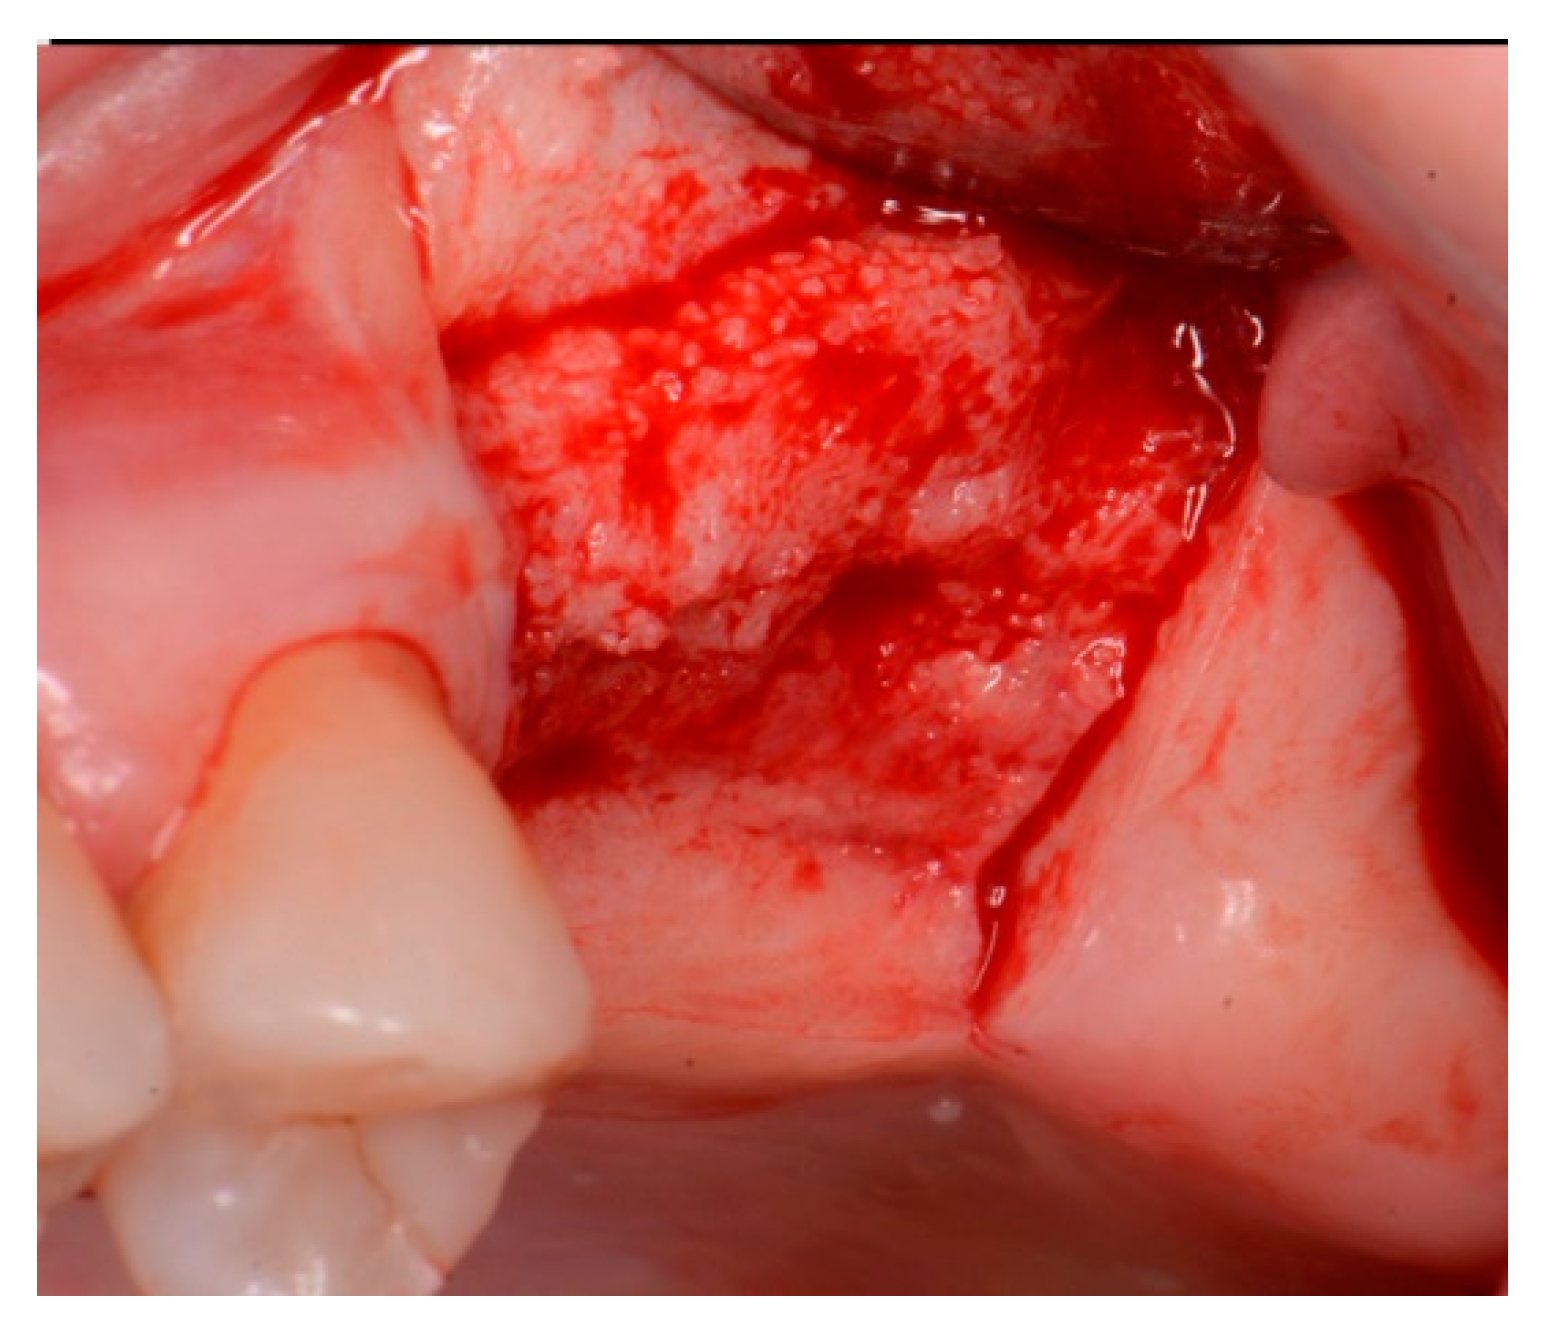

A critical question is about what happens histologically to the graft and at what stage during healing. For example, when delayed socket grafting was performed at a site where a large defect was present following extraction (Figure 18, left), a healing period of 3 weeks post-extraction was needed, allowing primary closure post-graft. This gives us more predictability and simpler surgery, plus two attempts to clean the site. EthOss graft material was placed into the socket (Figure 18, middle) and primary closure with the flap was achieved and secured with sutures (Figure 18, right). Intraoral physical exam and radiographic measurement showed all sites to have regenerated vertically 3–6 mm and horizontally 4–6 mm with new host bone allowing for successful placement of the implants. A core sample was obtained from one case to confirm the series to be in line with earlier findings. Histology was performed by core biopsy at 10 weeks following graft placement and demonstrated well-preserved reactive (woven) trabecular bone with intertrabecular tissue composed of uniformly collagen-rich myofibroblastic tissue and 60% of the core consisting of bone (Figure 19).

Figure 18.

Delayed socket grafting with flap exposure of the site (left), placement of EthOss graft to fill the defect (middle) and flap placement to achieve primary closure (right).